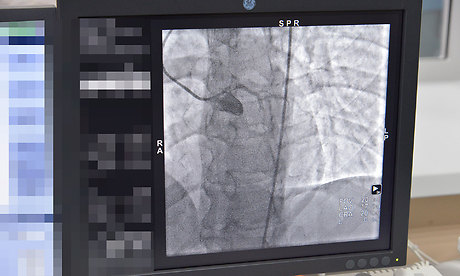

13 марта Губернатор Брянской области Александр Богомаз посетил отделение рентгенохирургических методов диагностики и лечения второго регионального центра для лечения больных с сердечно-сосудистой патологией Брянской городской больницы № 1.

Главный врач Брянской городской больницы № 1 Константин Воронцов сообщил, что с февраля 2018 года в ГАУЗ «Брянская городская больница № 1» функционирует новое структурное отделение рентгенохирургических методов диагностики и лечения. Данное отделение открыто благодаря приобретению дорогостоящего оборудования -ангиографической установки «Инова» за счет денежных средств, выделенных областным бюджетом в сумме 37 млн. рублей. Это позволит открыть второй региональный центр для лечения больных с сердечно-сосудистой патологией, применяя высокотехнологические методы лечения, а именно: стентирование коронарных сосудов, сосудов нижних конечностей; оперативное лечение сосудистой патологии головного мозга.

В настоящее время в отделении проводится коронарография пациентам с сердечно-сосудистой патологией. В дальнейшем, при получении лицензии на проведение высокотехнологической медицинской помощи, будет проводиться стентирование сосудов.

В 2018 году запланировано проведение 300 коронарографий и 250 стентирований сосудов.